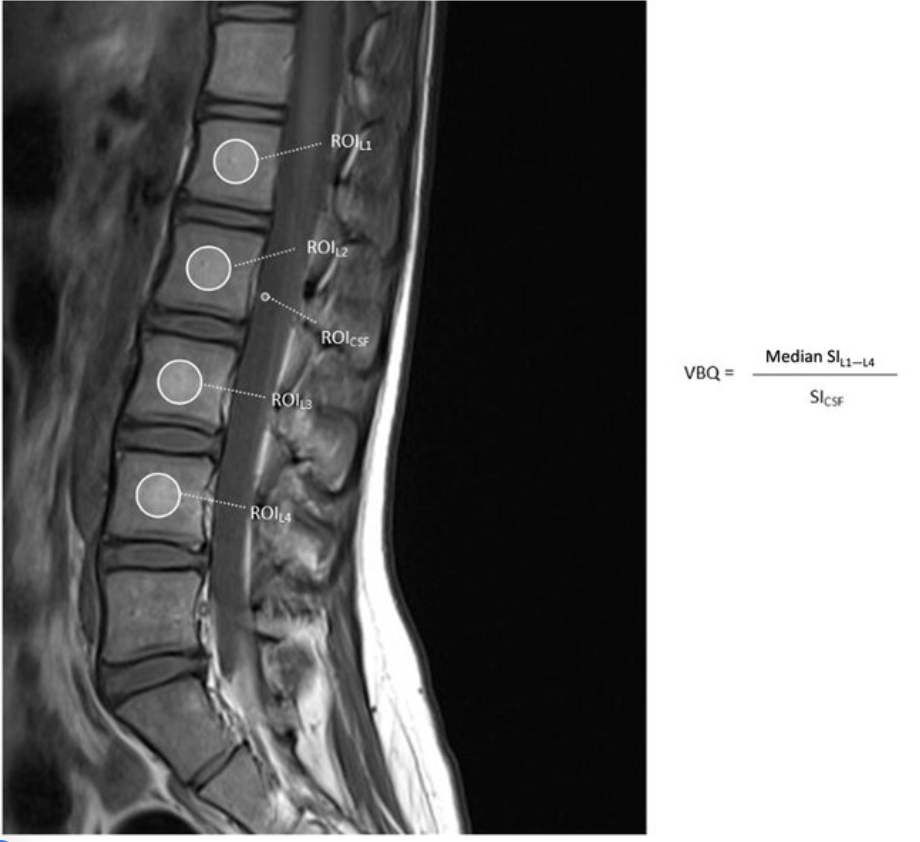

Adapted from: Non-contrast-enhanced T1-weighted MRI of the lumbar spine demonstrating regions of interest used to calculate the L1–L4 vertebral body quality (VBQ) score, Journal of Clinical Medicine (Accessed on 03 Jan 2026).

The Vertebral Bone Quality (VBQ) score is an MRI-based measure that quantifies vertebral bone marrow signal intensity to assess bone quality. It serves as an opportunistic screening tool for osteoporosis and bone quality assessment in patients undergoing spine imaging. The VBQ score reflects bone marrow composition, with higher scores indicating increased fat content in the marrow (which correlates with decreased bone quality). The score is calculated as a ratio of vertebral body signal intensity to cerebrospinal fluid (CSF) signal intensity on non-contrast T1-weighted MRI sequences.

• Obtain midsagittal T1-weighted MRI images of the lumbar spine

• Place regions of interest (ROI) within the trabecular bone of L1-L4 vertebral bodies to measure median signal intensity

• A separate region of interest is placed within the cerebrospinal fluid (CSF) at the level of the conus or cauda equina to serve as an internal reference. Measure the signal intensity of CSF, typically at the L2 or L3 level (both are comparable)

• Calculate VBQ score = (median signal intensity of L1-L4 vertebrae) / (signal intensity of CSF), producing a normalized ratio that can be compared across patients and scanners.